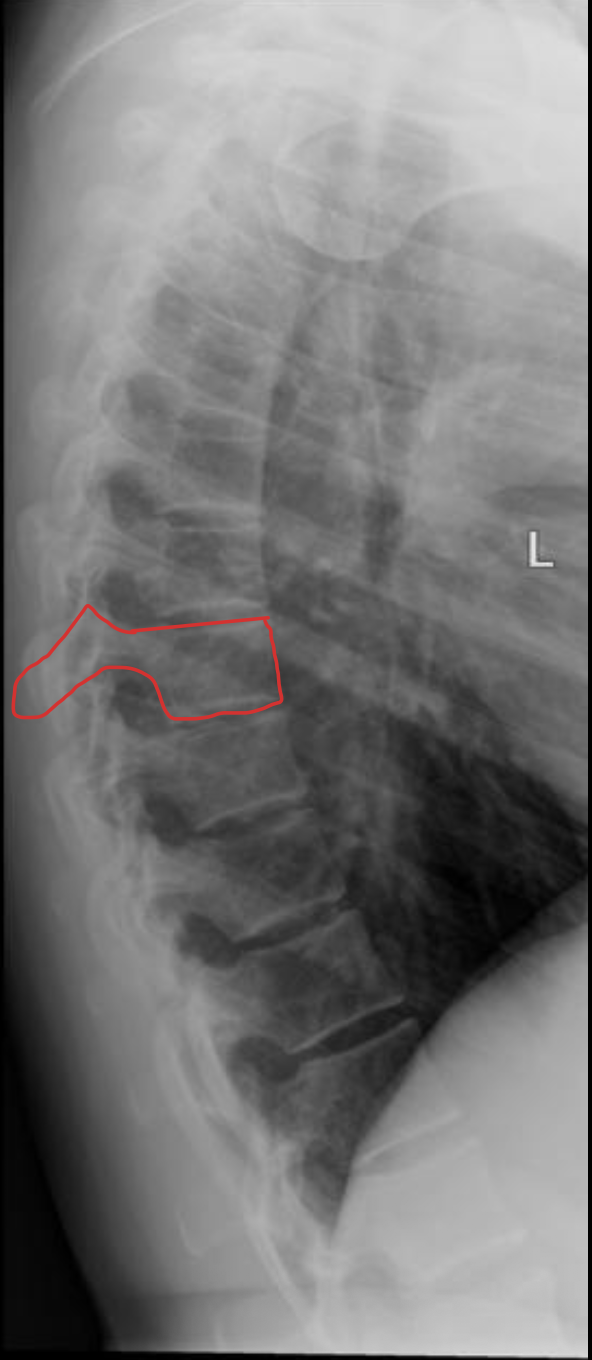

胸椎

THORACIC

T1

T2

T3

T4

T5

T6

T7

T8

T9